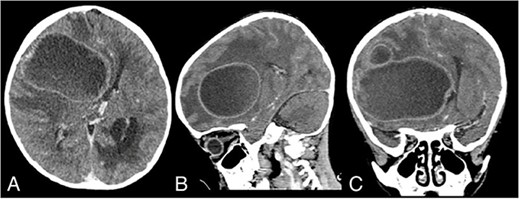

On admission, his GCS was E2M4V2 with a blood pressure of 88/58 mmHg, heart rate of 94 times per minute, respiratory rate of 33 times per minute, temperature of 36.6°C, and oxygen saturation of 86%. Auscultation revealed a systolic murmur. The patient also had cyanosis and clubbing fingers. The patient was malnourished, with a weight of 13 kg and a height of 98 cm. His chest X-ray revealed a cardiomegaly. Head CT scan revealed a hypodense lesion on the right frontotemporoparietal lobe with a size of 5.7 × 6.5 × 7.7 cm with tentacle-like edema on its surrounding, which gave a ring-enhancement after contrast administration (Fig. 1A–C). On echocardiography, there was a significant VSD with a bidirectional shunting.

Admission contrast head CT scan showing a large hypodense lesion with ring-enhancement on the right frontotemporoparietal lobe; (A) axial view; (B) sagittal view; (C) coronal view.